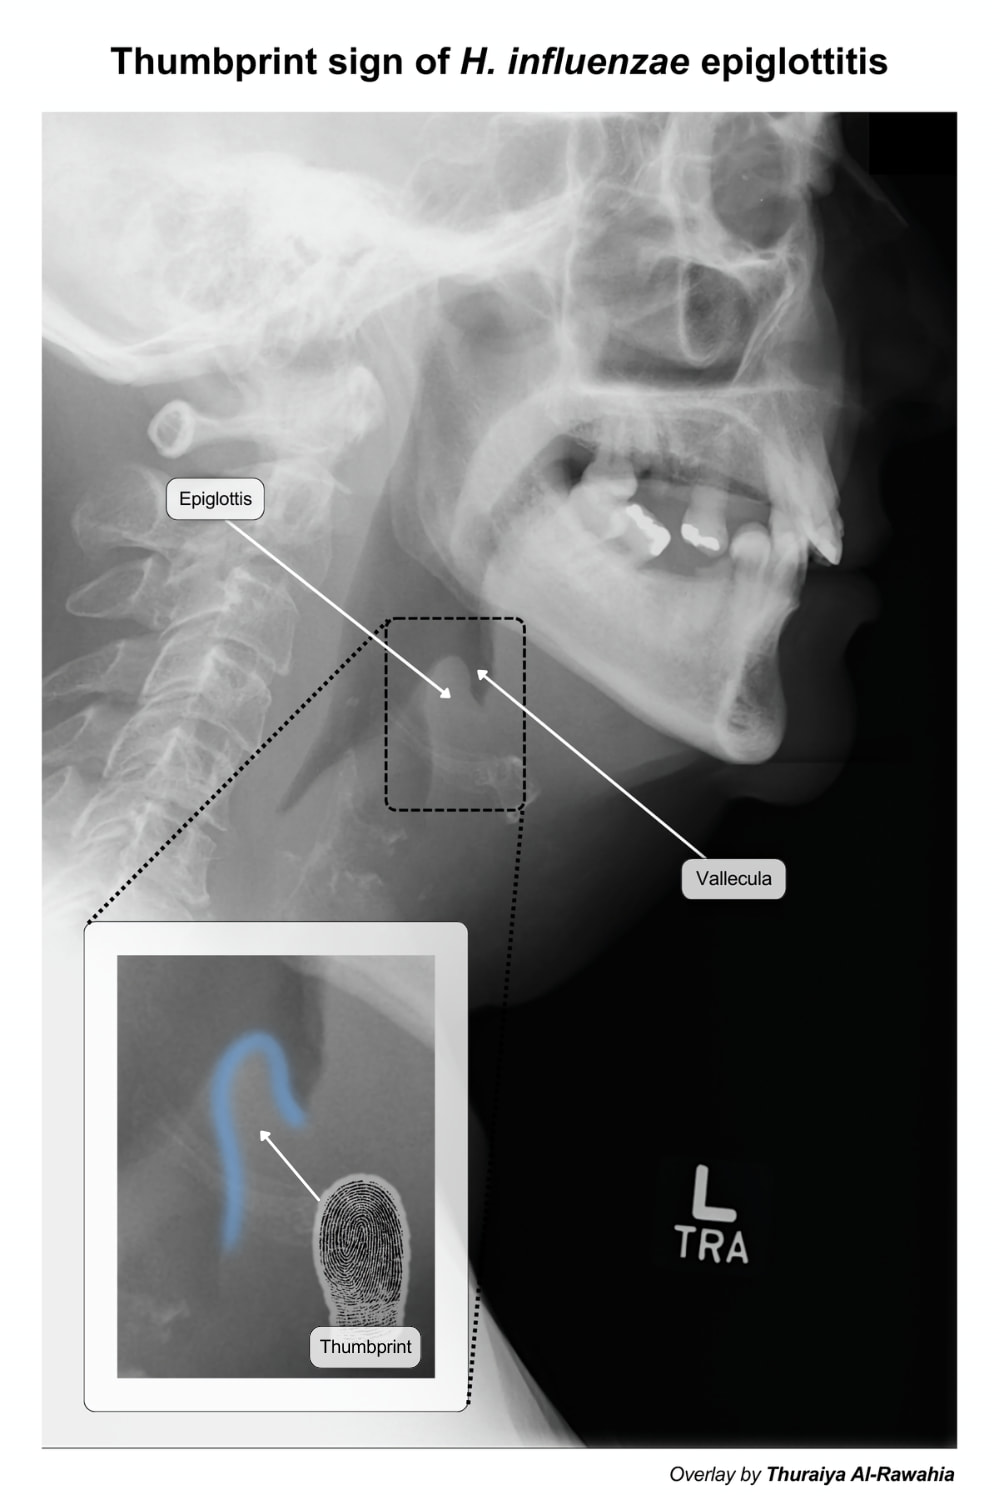

Tons of illustrations, diagrams, and annotated images have been added! A few are shown below. Thanks to @ahmedafifi, @beejumm, @thuthiii, and @MarcosZan! They will be suggested and added to the deck shortly.